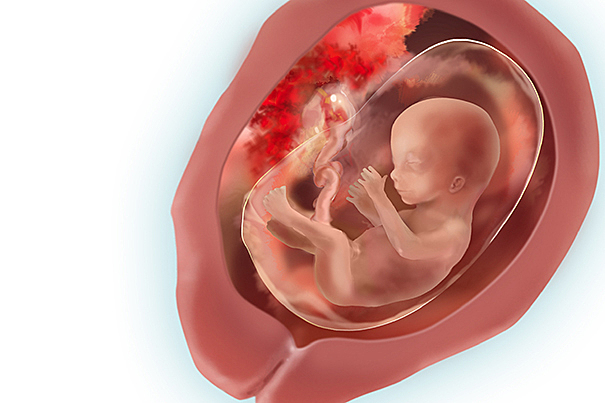

-Ya están formados los órganos vitales

-Se empieza a formar el paladar y las papilas gustativas, se encuentran en toda la boca y no solo en la lengua, sino alrededor de ella, en el área de los labios e incluso en las mejillas.

-El feto ahora chupa el pulgar, juega con el cordón umbilical. Estos movimientos tienen un objetivo: ejercitar la musculatura en desarrollo.